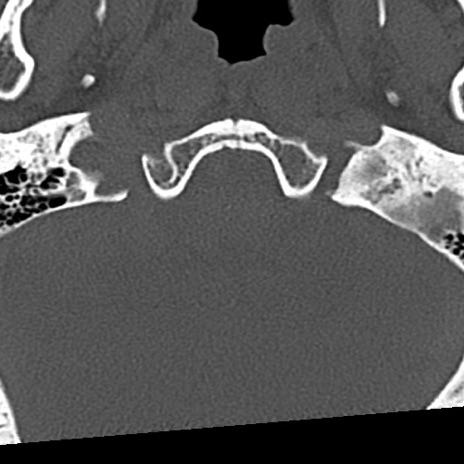

頚椎CT

横断像